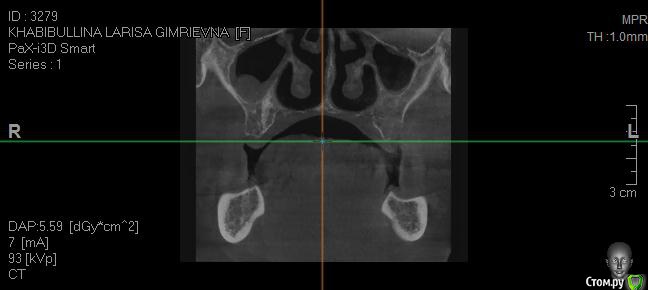

Реальная картина на сегодня:

1.        Верхняя челюсть – полная адентия (имеется один корень клык)

2.        Нижняя челюсть – протез просел – в коррекции отказано, (с левой стороны протез держится на отдельно стоящем подвижном зубе, т.к. распалось соединение с зубным рядом.)

- Нижняя челюсть выдвинулась в перед (возрастной мезиальный прикус)

- Нижняя челюсть гипермобильна , дисфункция ВНЧС, хрустит прикус прогенически,  (диагноз ЧЯХ (в лечение отказан) Рот открывается рывком (безболезненно)

- Нужно ли наращивать кость в челюсти?

2. Достаточно ли кости для проведение имплантации? Нужна ли ринопластика?